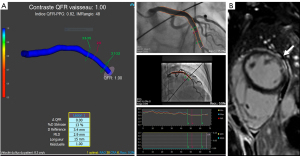

Novel Stentless Strategy With Perfusion and Drug-Coated Balloons for Treating Acute Coronary Syndrome www.jscai.org May 9, 2026, 10:10 a.m.

Stentless treatment of acute coronary syndrome uses gradual, prolonged predilation. A perfusion balloon combined with a drug-coated balloon was used. The stentless strategy achieved successful revascularization in most patients. No acute occlusion or in-hospital major adverse cardiac events were reported. A low incidence of target vessel failure at 24 months was reported.

Slow flow and no reflow after percutaneous coronary intervention eurointervention.pcronline.com May 9, 2026, 9:31 a.m.

Primary percutaneous coronary intervention is currently the standard of care for the treatment of acute ST-segment elevation myocardial infarction (STEMI). While it can restore flow in the infarcted artery in the majority of cases, some patients experience the so-called “no-reflow” phenomenon, which consists of abnormal myocardial reperfusion occurring after the occluded coronary artery has been opened. It is caused by microvascular obstruction (MVO), and its pathogenesis is multifactorial, including myocardial ischaemia, distal embolisation, and ischaemia-reperfusion injury, combined with individual susceptibility. Currently, there is no consensus on pharmacological or interventional strategies which can prevent or treat it.